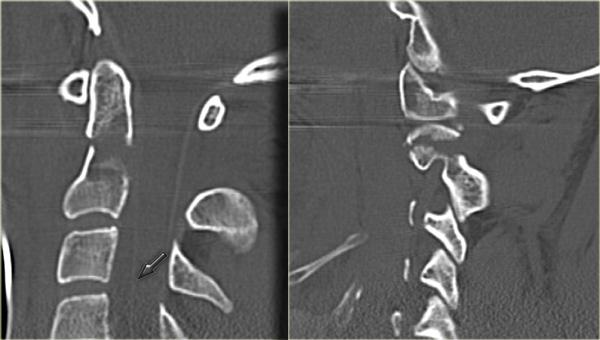

Bong gân tăng gấp (3)

MRI giải thích tình trạng thần kinh của bệnh nhân này.

Các dấu hiệu trên MRI bao gồm:

- Tổn thương mô mềm nặng nề ở các cấu trúc cạnh sống phía sau, đặc biệt tại mức C5-6, nơi dây chằng gian gai và dây chằng vàng bị đứt

- Rách đĩa đệm C5-6 với di lệch ra phía sau C5

- Phù nề tủy sống lan rộng

Tiếp tục với hình ảnh mặt cắt axial.

Hình ảnh axial cho thấy tổn thương tủy sống và ngoài ra còn có sự vắng mặt của khoảng trống dòng chảy (flow void) ở động mạch đốt sống phải.

Điều này gợi ý huyết khối do bóc tách động mạch.

Kết luận, bệnh nhân này không có gãy xương, nhưng có bong gân tăng gấp nặng kèm thoát vị đĩa đệm cấp tính, tổn thương tủy sống không xuất huyết và huyết khối động mạch đốt sống.

Chụp mạch cộng hưởng từ (MRA) xác nhận tắc nghẽn động mạch đốt sống phải.